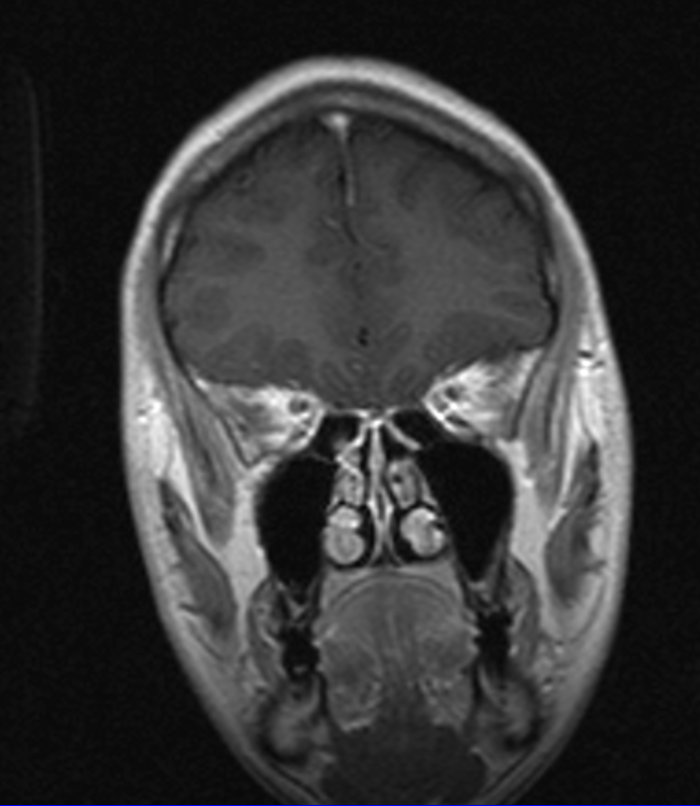

Я снова у нейрохирургов, сделали МРТ.

Снимки выбрал самые интересные.

Нейрохирурги сказали, что это вообще редкость, когда аденома гипофиза прорастает в кость. На счет операции они пока точно сказать не могут. Сказали, что они ее всю не уберут. Могут ее уменьшить, а потом надо будет ее добить химио/лучевой терапией. Оперировать в 40 больнице и еще в нескольких других не возьмутся, поскольку опухоль большая, и они все равно направляют обратно в онкологию. Сказали снова идти к эндокринологу (результаты анализов только в тот день получил).